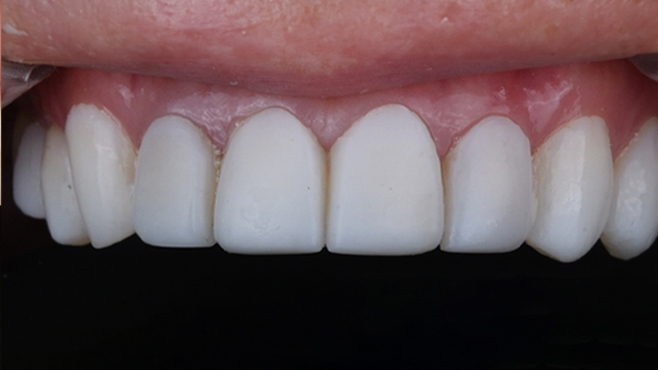

임플란트 가격 반 값으로 전체 보철 치료하기?!

2026.01.07